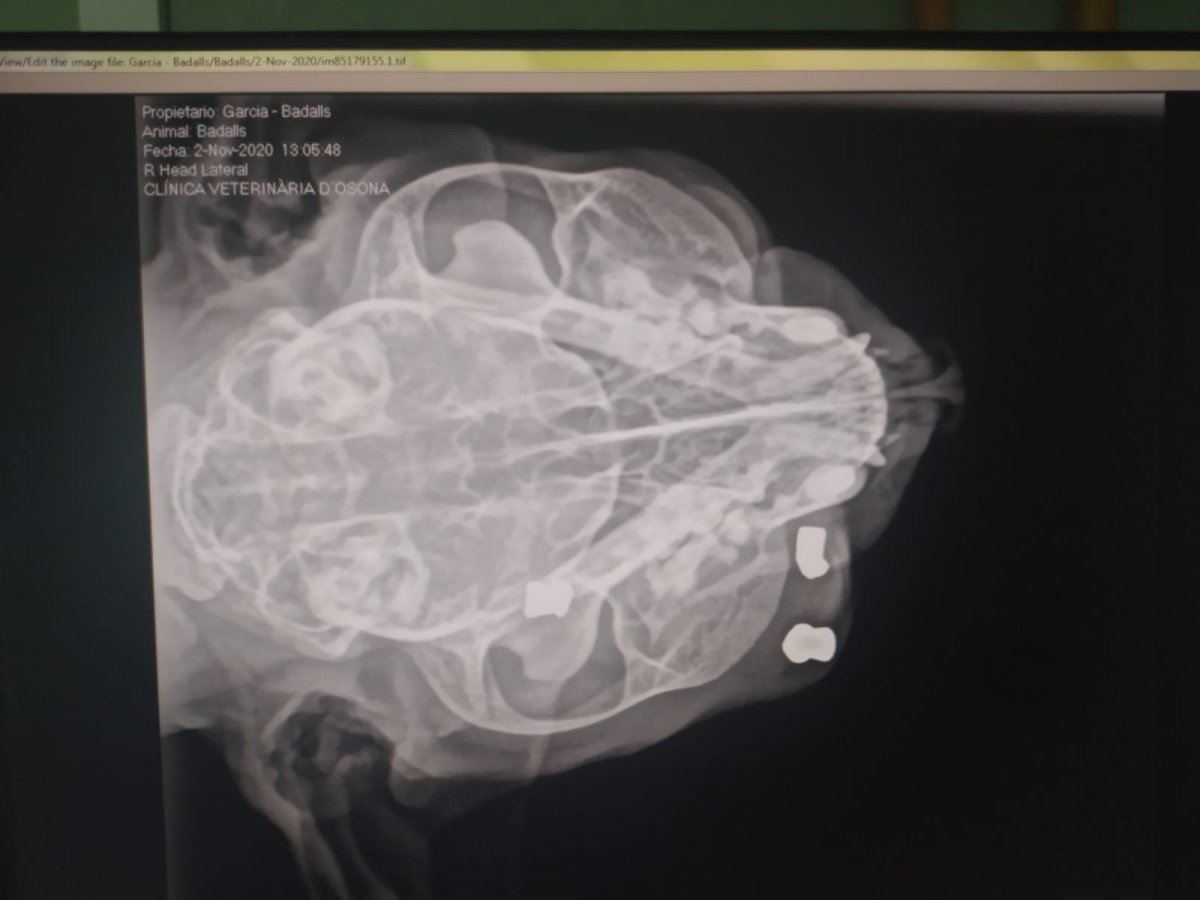

Veïns del barri dels Caputxins de Vic han presentat una denúncia als Mossos d’Esquadra després que el seu gat, anomenat Badalls, hagi rebut l’impacte de tres balins que l’han deixat sense un ull. El propietari, Pol Garcia, explica que el gat se sol passejar per una illa de cases del barri i que diumenge al vespre l’animal tornava amb una ferida a l’ull. D’entrada van creure que podria haver estat a causa d’una baralla però en anar a la clínica veterinària, a través de les ràdiografies, van observar la presència de tres balins, que haurien estat la causa de la ferida.

Després de l’operació que li van fer d’urgència, l’animal ha perdut un ull. De moment es desconeix qui podria haver disparat.